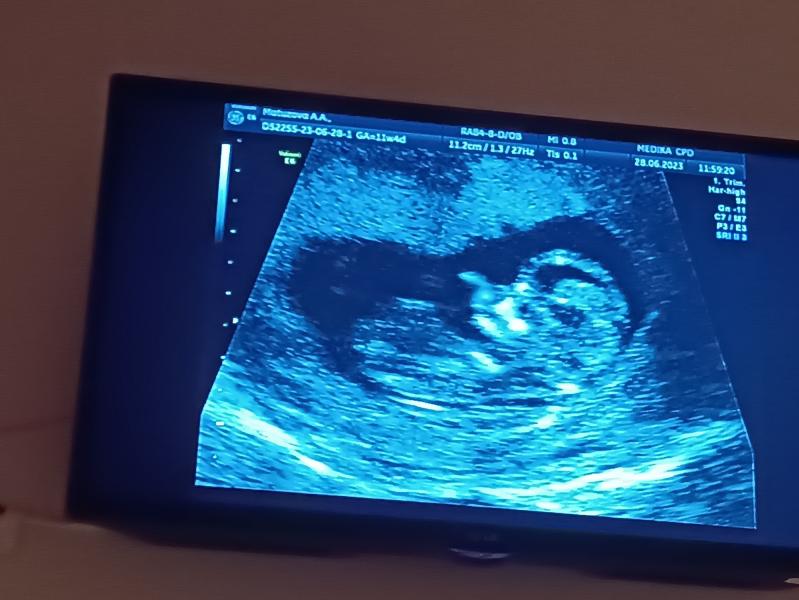

11 недель скрининг показал 12 недель, девочка? Переживаю, будет ли дочка такой же активной, как Надежда!

Маленький живчик , была на скрининге в 11 и 4 дня , по итогу она на все 12 недель , предположили девочку 😭 если она будет , как Надежда , то я сойду с ума 😅